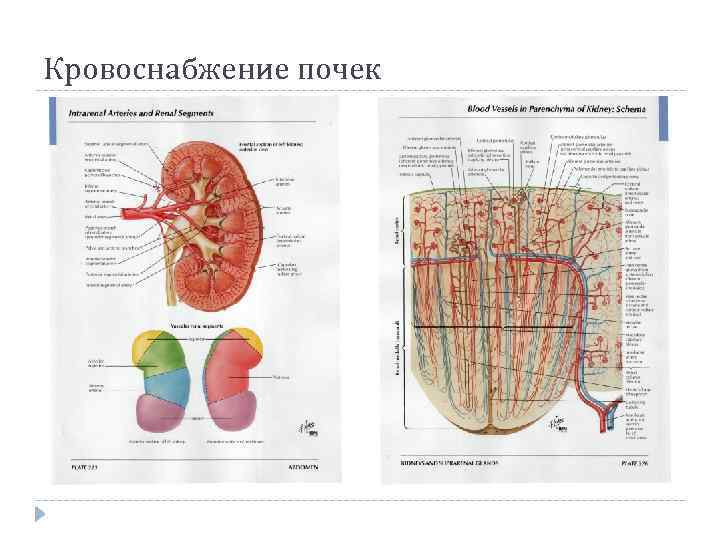

Кровоснабжение почек

Кровоснабжение почек